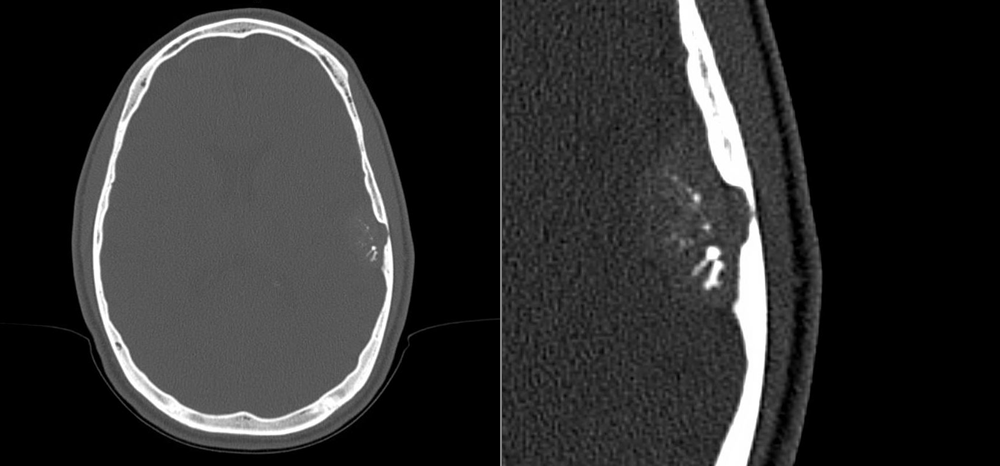

The axial non-contrast CT of the head (left) and detail (right) are shown here. The radiologist describes a “spoke wheel” pattern of calcification in an extra-axial mass.

What is the most likely diagnosis?